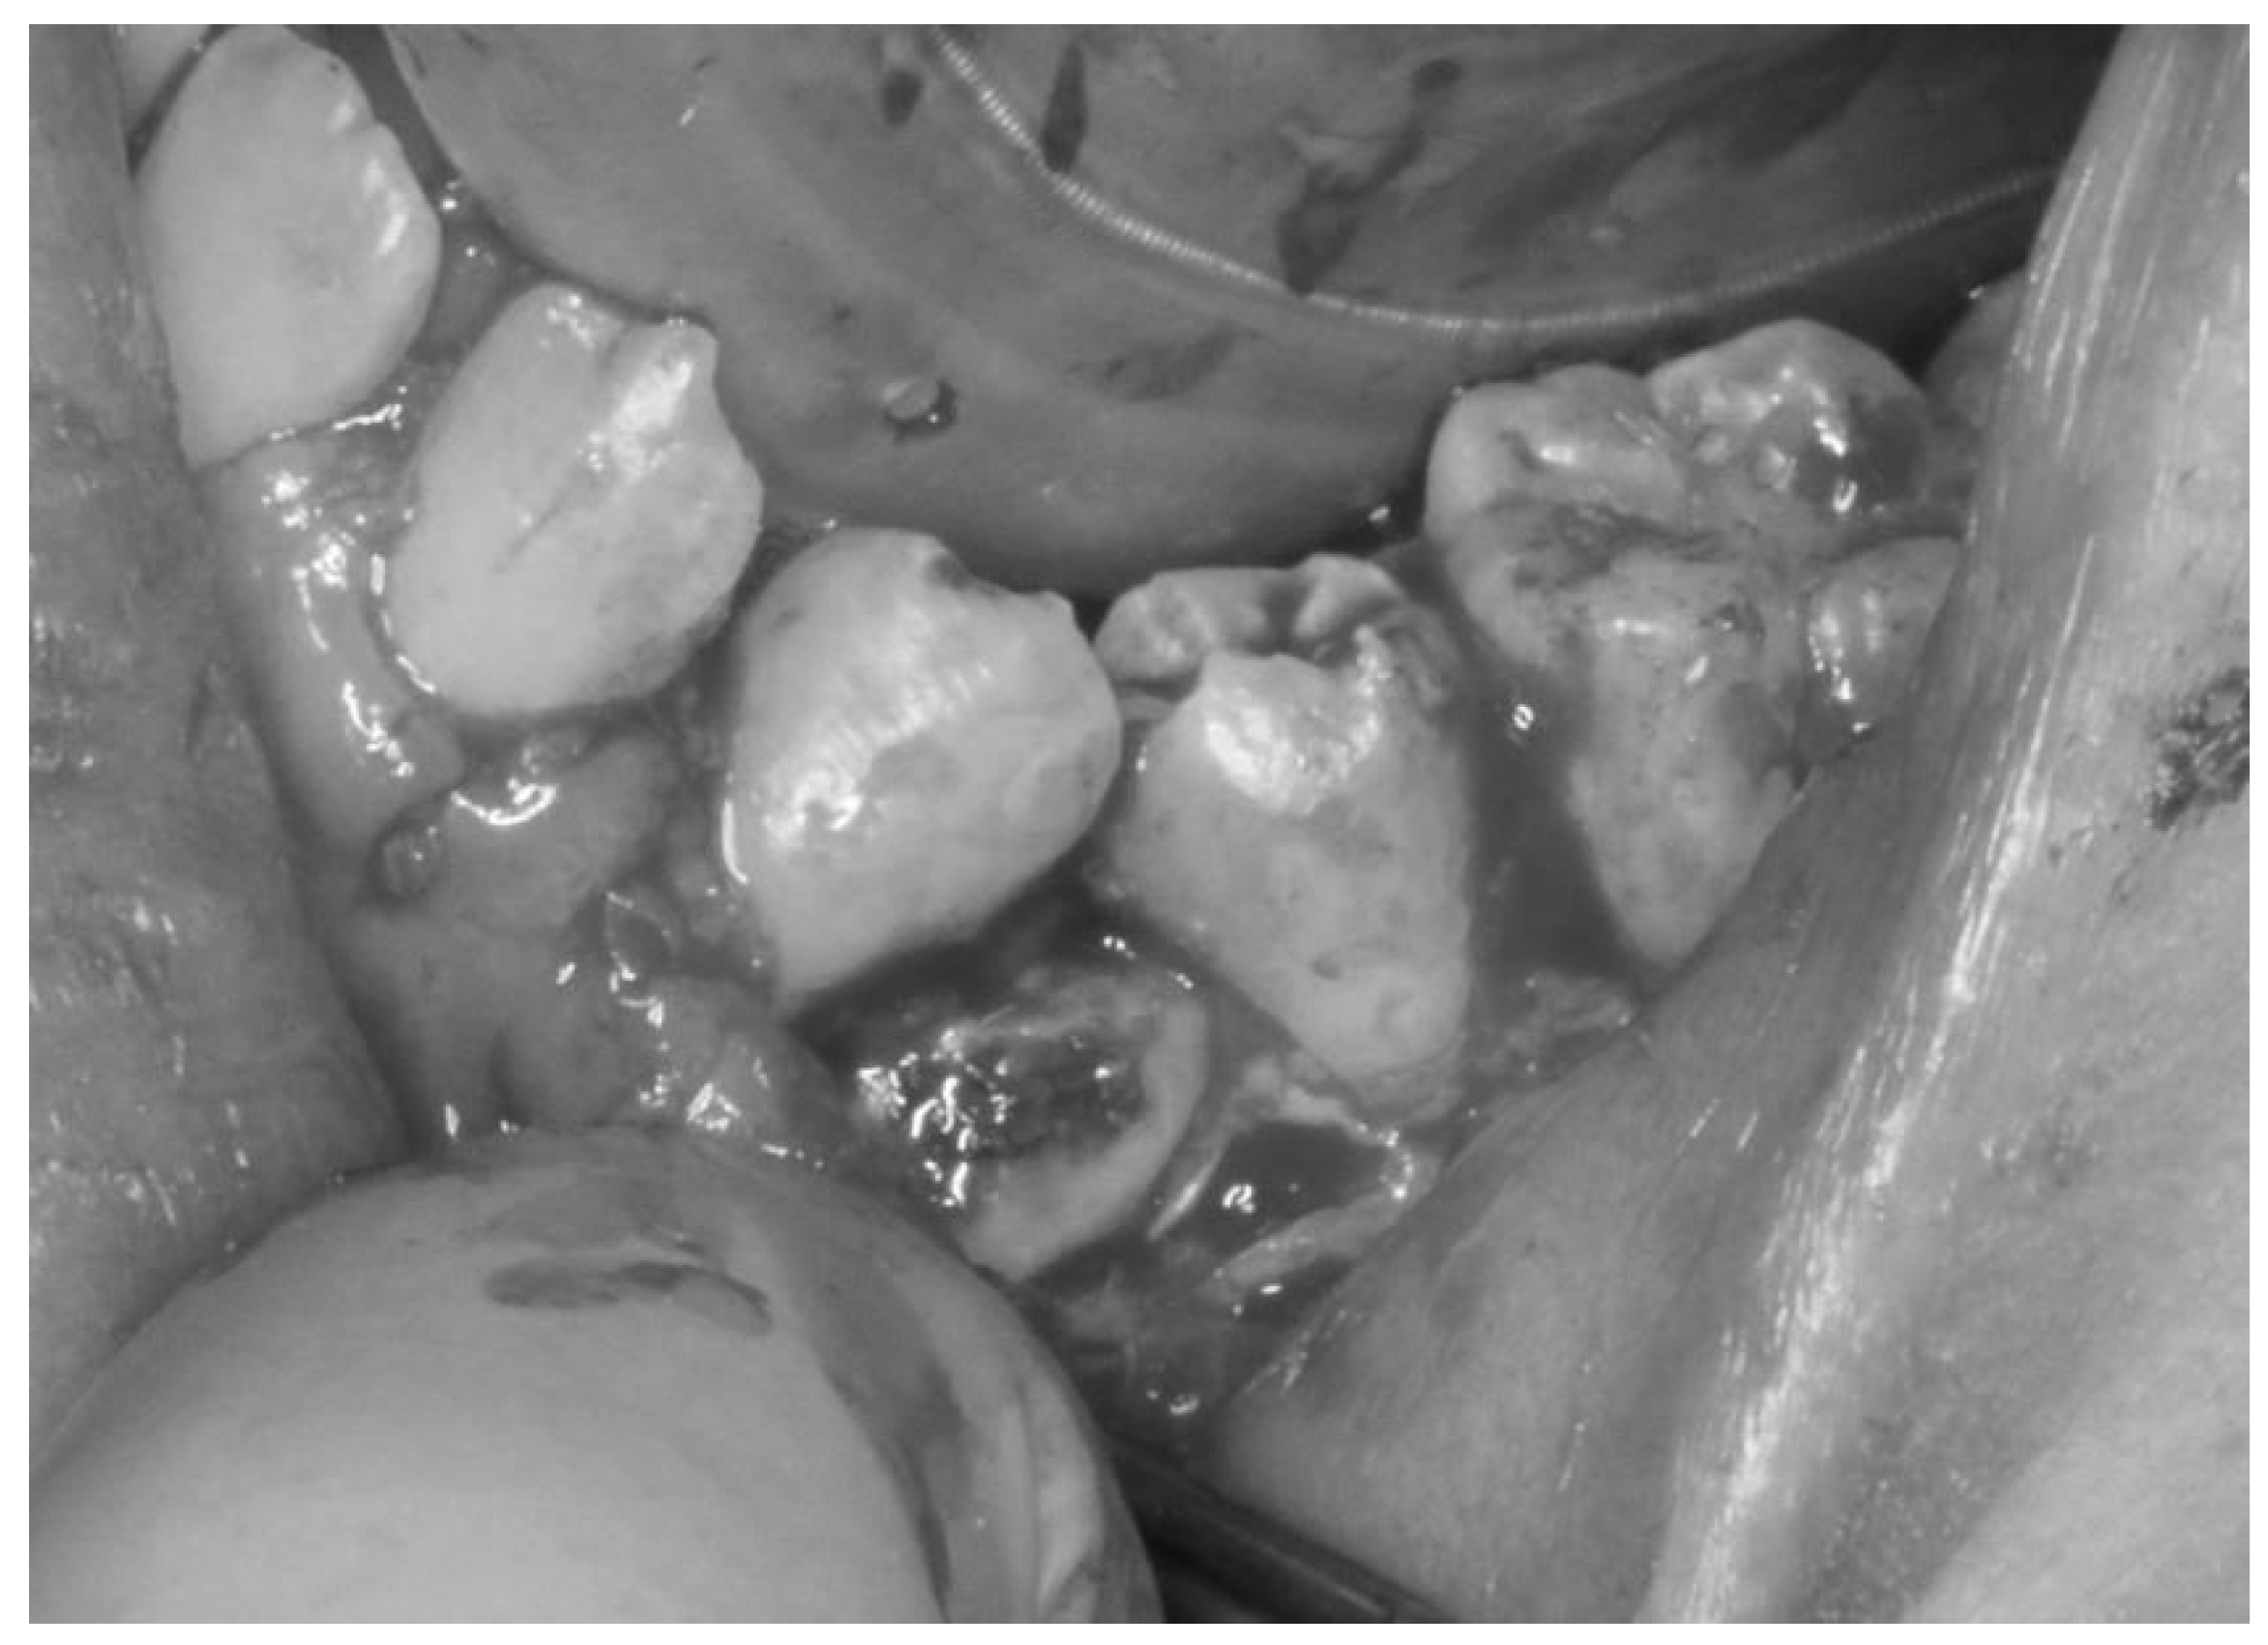

The treatment was carried out under general anesthesia with the aim of improving his oral hygiene. Initial observation of his oral condition was carefully completed. Dental X-ray and intraoral images during the administration of analgesic were obtained before starting the surgery (Figure 2 and Figure 3). A local anesthetic, proparacaine hydrochloride/felypressin (Citanest-Octapressin Cartridge for Dental use®), was injected into the affected area. An incision was made around the area along the cervical region and the oral mucosa was removed, which revealed the concealed tooth. It was observed from the left buccal side, but it was considered to be partially ankylosed. Then, a part of the target tooth was histopathologically examined to determine if there was any sign of ankylosis around it. Eventually, the tooth was divided into parts for smooth extraction, and the incision was closed using absorbable sutures (Figure 4).

Figure 4.

Condition of the target tooth during oral surgery. The target tooth was visible after removal of the oral mucosa, and the tooth was divided into two parts and extracted.

RESULTS

The oral surgery was successful in improving the patient’s oral hygiene, which resulted in a decreased risk of infection. The groove on his alveolar bone disappeared because of the extra space made by the extraction of the target tooth. However, his first and second premolars still leaned against the gum.

The histopathological analysis revealed some odontoclastic resorption cavities and absorption lines on the root of the extracted tooth, but there was no evidence of ankyloses (Figure 5).